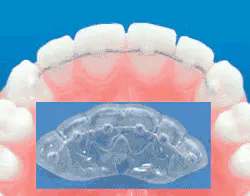

Once the changes or potential changes are indicated, we need to get in there and prevent them from occurring or worsening — with a final retainer, active retainer, or bruxism splint.